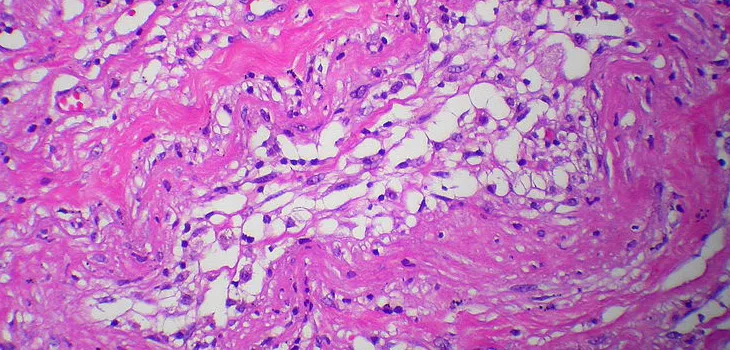

Il sistema Lipogems utilizza tessuto adiposo prelevato tramite lipoaspirazione per creare un materiale iniettabile. La tecnologia preserva l'integrità del tessuto adiposo, mantenendo la sua rete vascolare e la matrice extracellulare, supportando una migliore integrazione tissutale.

Il vantaggio unico di Lipogems è il mantenimento dell'ambiente rigenerativo completo del tessuto adiposo, che migliora la vitalità cellulare e la capacità rigenerativa. Le cellule mesenchimali presenti necessitano del supporto di altre cellule e proteine per esercitare i loro benefici curativi.